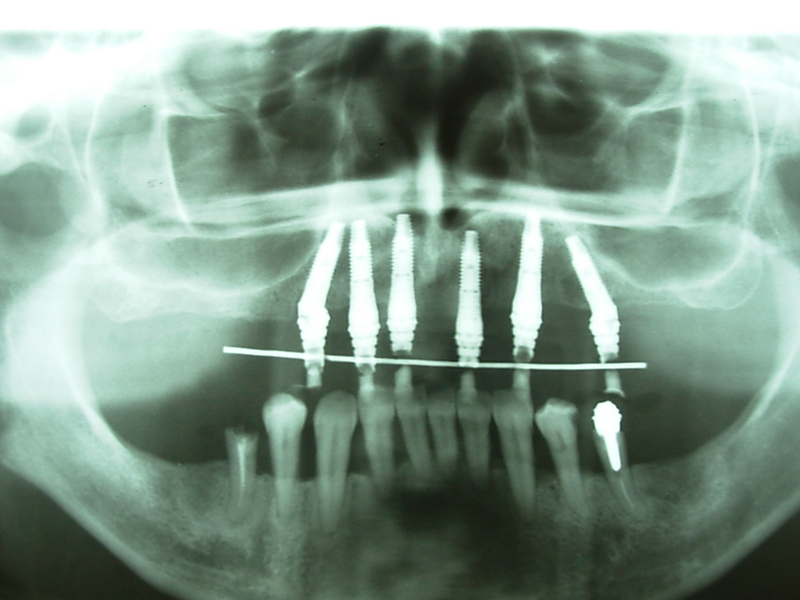

Na Clínica Pontes Odontologia, somos referência em implantes dentários em Fortaleza, oferecendo tratamentos de alta qualidade e tecnologia de ponta. Os implantes dentários são estruturas de titânio posicionadas cirurgicamente no osso maxilar ou mandibular para substituir as raízes dos dentes ausentes. Essa técnica permite a fixação de próteses personalizadas, restaurando a função mastigatória, a estética e a autoestima dos nossos pacientes.